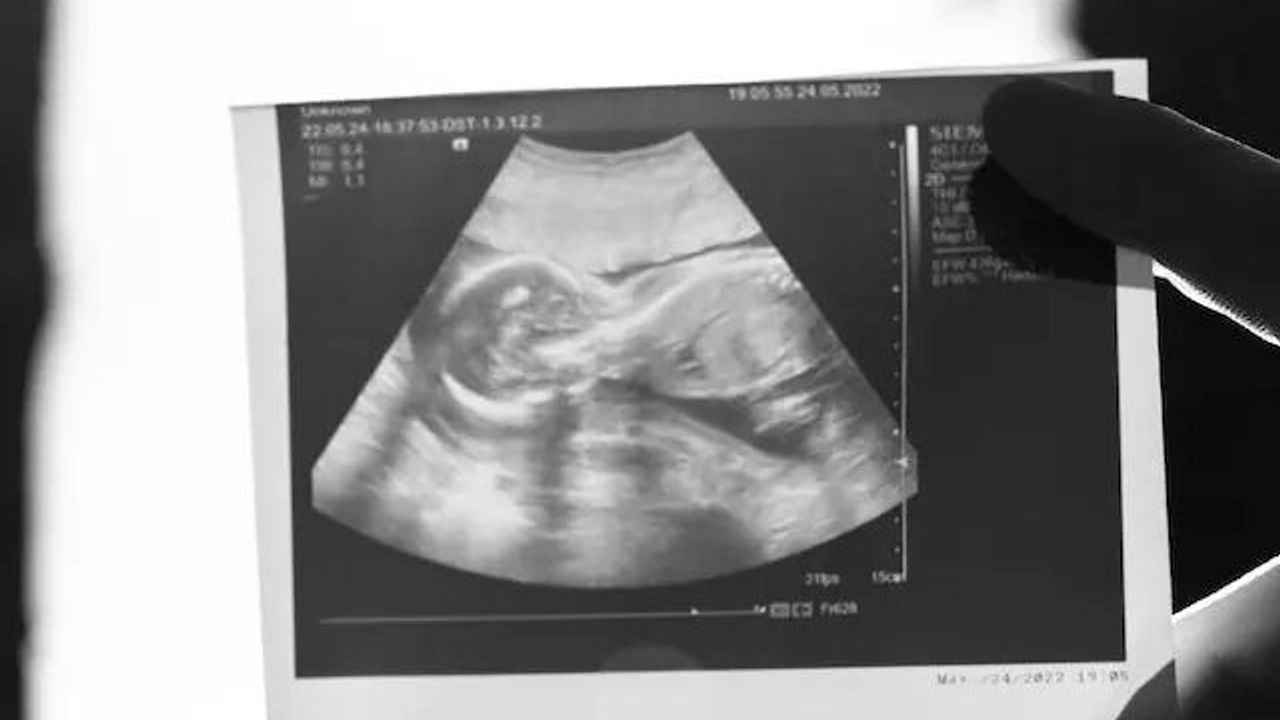

Kadınların ani durum değişmelerinde genellike gebelikten şüphelenilir. Bu şüphelerin en belirgin özelliklerinden biri de mide bulantısıdır. Peki hamilelikte mide bulantısı ne zaman başlar? Sizler için ayrıntıları haberimizde derledik.

Anne adaylarında genellikle düzenli adet olan kadınların adet gecikmesi gebeliğin en önemli belirtisidir. Sonrasında mide bulantısı, kusma, baş dönmesi, göğüslerde şişlik ve hassasiyet gibi semptomlar da hamileliğin önemli belirtilerindendir.